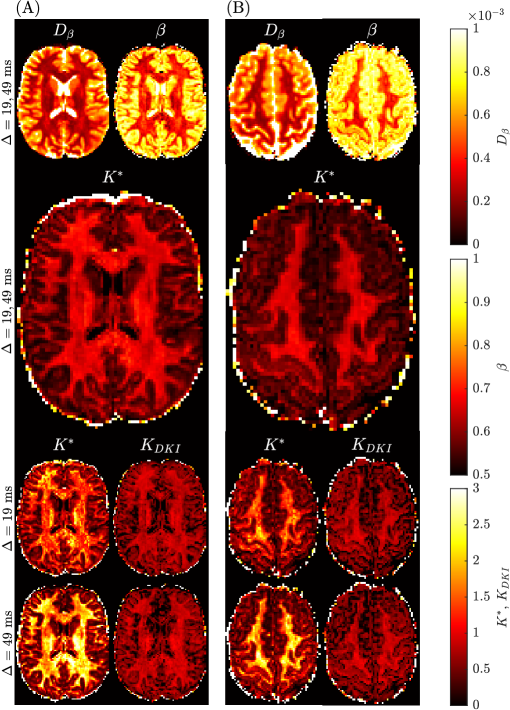

2.4 Benchmark mean kurtosis in the brain

The benchmark mean kurtosis estimation in the brain is established using the entire b-value range with all diffusion encoding directions available in the Connectome 1.0 DW-MRI data. For two subjects in different slices, Figure 6 provides the spatially resolved maps of mean kurtosis computed using the sub-diffusion method (i.e., Ksuperscript𝐾K^{*}) with one or two diffusion times, and using the standard method (i.e., KDKIsubscript𝐾𝐷𝐾𝐼K_{DKI}) considering the two distinct diffusion times. First, we notice a degradation in the KDKIsubscript𝐾𝐷𝐾𝐼K_{DKI} image with an increase in diffusion time. Second, the use of a single diffusion time with the sub-diffusion model leads to Ksuperscript𝐾K^{*} values which are larger than either the KDKIsubscript𝐾𝐷𝐾𝐼K_{DKI} values or Ksuperscript𝐾K^{*} values generated using two diffusion times. Third, the quality of the mean kurtosis map appears to visually be best when two diffusion times are used to estimate Ksuperscript𝐾K^{*}. Superior grey-white matter tissue contrast (TC) was found for the Ksuperscript𝐾K^{*} map (TC=1.73𝑇𝐶1.73TC=1.73), compared to the KDKIsubscript𝐾𝐷𝐾𝐼K_{DKI} maps (TC=0.80𝑇𝐶0.80TC=0.80 for the Δ=19 msΔ19 ms\Delta=19\text{ ms} dataset and TC=1.01𝑇𝐶1.01TC=1.01 for the Δ=49 msΔ49 ms\Delta=49\text{ ms} dataset).

Refer to caption

Figure 6: Spatially resolved maps of mean kurtosis shown for two example slices and two different subjects, Subject 3 rescan slice 71 (Panel A) and Subject 5 slice 74 (Panel B) from the Connectome 1.0 DW-MRI data. Individual maps were generated using the sub-diffusion model framework (Ksuperscript𝐾K^{*}), as well as using the traditional approach (KDKIsubscript𝐾𝐷𝐾𝐼K_{DKI}). The diffusion times, ΔΔ\Delta, used to generate each plot are provided for each case. We consider the mean kurtosis maps using two diffusion times (Δ=19, 49msΔ1949ms\Delta=19,\leavevmode\nobreak\ 49$\mathrm{m}\mathrm{s}$) as the benchmarks.